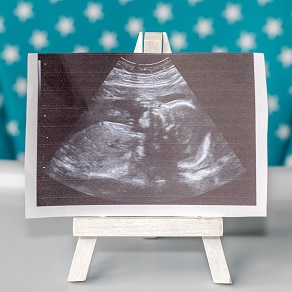

УЗИ ребёнка в животе: что показывает исследование?

Как выглядит ребенок на УЗИ по неделям, позволяет отслеживать развитие плода и оценивать его соответствие нормам. Исследование показывает анатомию органов, двигательную активность и положение ребенка в матке, а также состояние плаценты и околоплодных вод. Регулярные УЗИ помогают своевременно выявить возможные осложнения и контролировать здоровье как матери, так и ребенка на всех этапах беременности.

В первом триместре на плановом скрининге УЗИ ребенка в животе на фото виден формирующийся эмбрион, напоминающий светлое пятно с четкими контурами. Врач измеряет основные параметры развития, включая копчико-теменной размер и толщину воротникового пространства.

Во втором триместре изображение демонстрирует полностью сформированного ребенка с хорошо видимыми внутренними органами и конечностями. На этом этапе можно рассмотреть черты лица, позвоночник и определить пол ребенка.

В третьем триместре УЗИ показывает пропорции доношенного ребенка, его положение в матке и готовность к родам. Из-за ограниченного пространства сложно разглядеть ребенка полностью, но можно оценить основные параметры развития и состояние плаценты.

На ранних сроках беременности развитие ребенка на фото внешне напоминает маленькое полупрозрачное зернышко. К 6-7 неделям он выглядит как изогнутая трубочка с заметным утолщением в области головы и зачатками конечностей в виде бугорков. Уже к концу первого триместра плод приобретает отчетливые человеческие черты, можно различить глаза, нос, рот и сформированные пальцы на руках и ногах.

Да, УЗИ является основным методом оценки развития плода. При каждом исследовании врач измеряет ключевые параметры (размер головы, длина бедренной кости, окружность живота) и сравнивает их с нормативными значениями для конкретного срока беременности. Одновременно оценивается анатомия внутренних органов, двигательная активность и состояние плаценты. Три плановых скрининга позволяют комплексно отслеживать развитие всех систем организма плода и своевременно выявлять возможные отклонения.